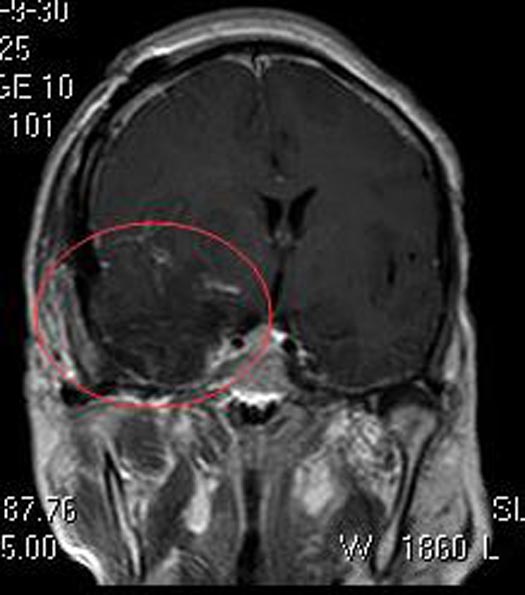

术后陈女士神志清醒,头痛症状明显较前好转。病理结果提示:混合型脑膜瘤 WHO I级。

▲术后MR